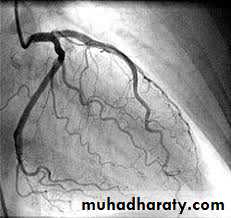

Coronary angiography.